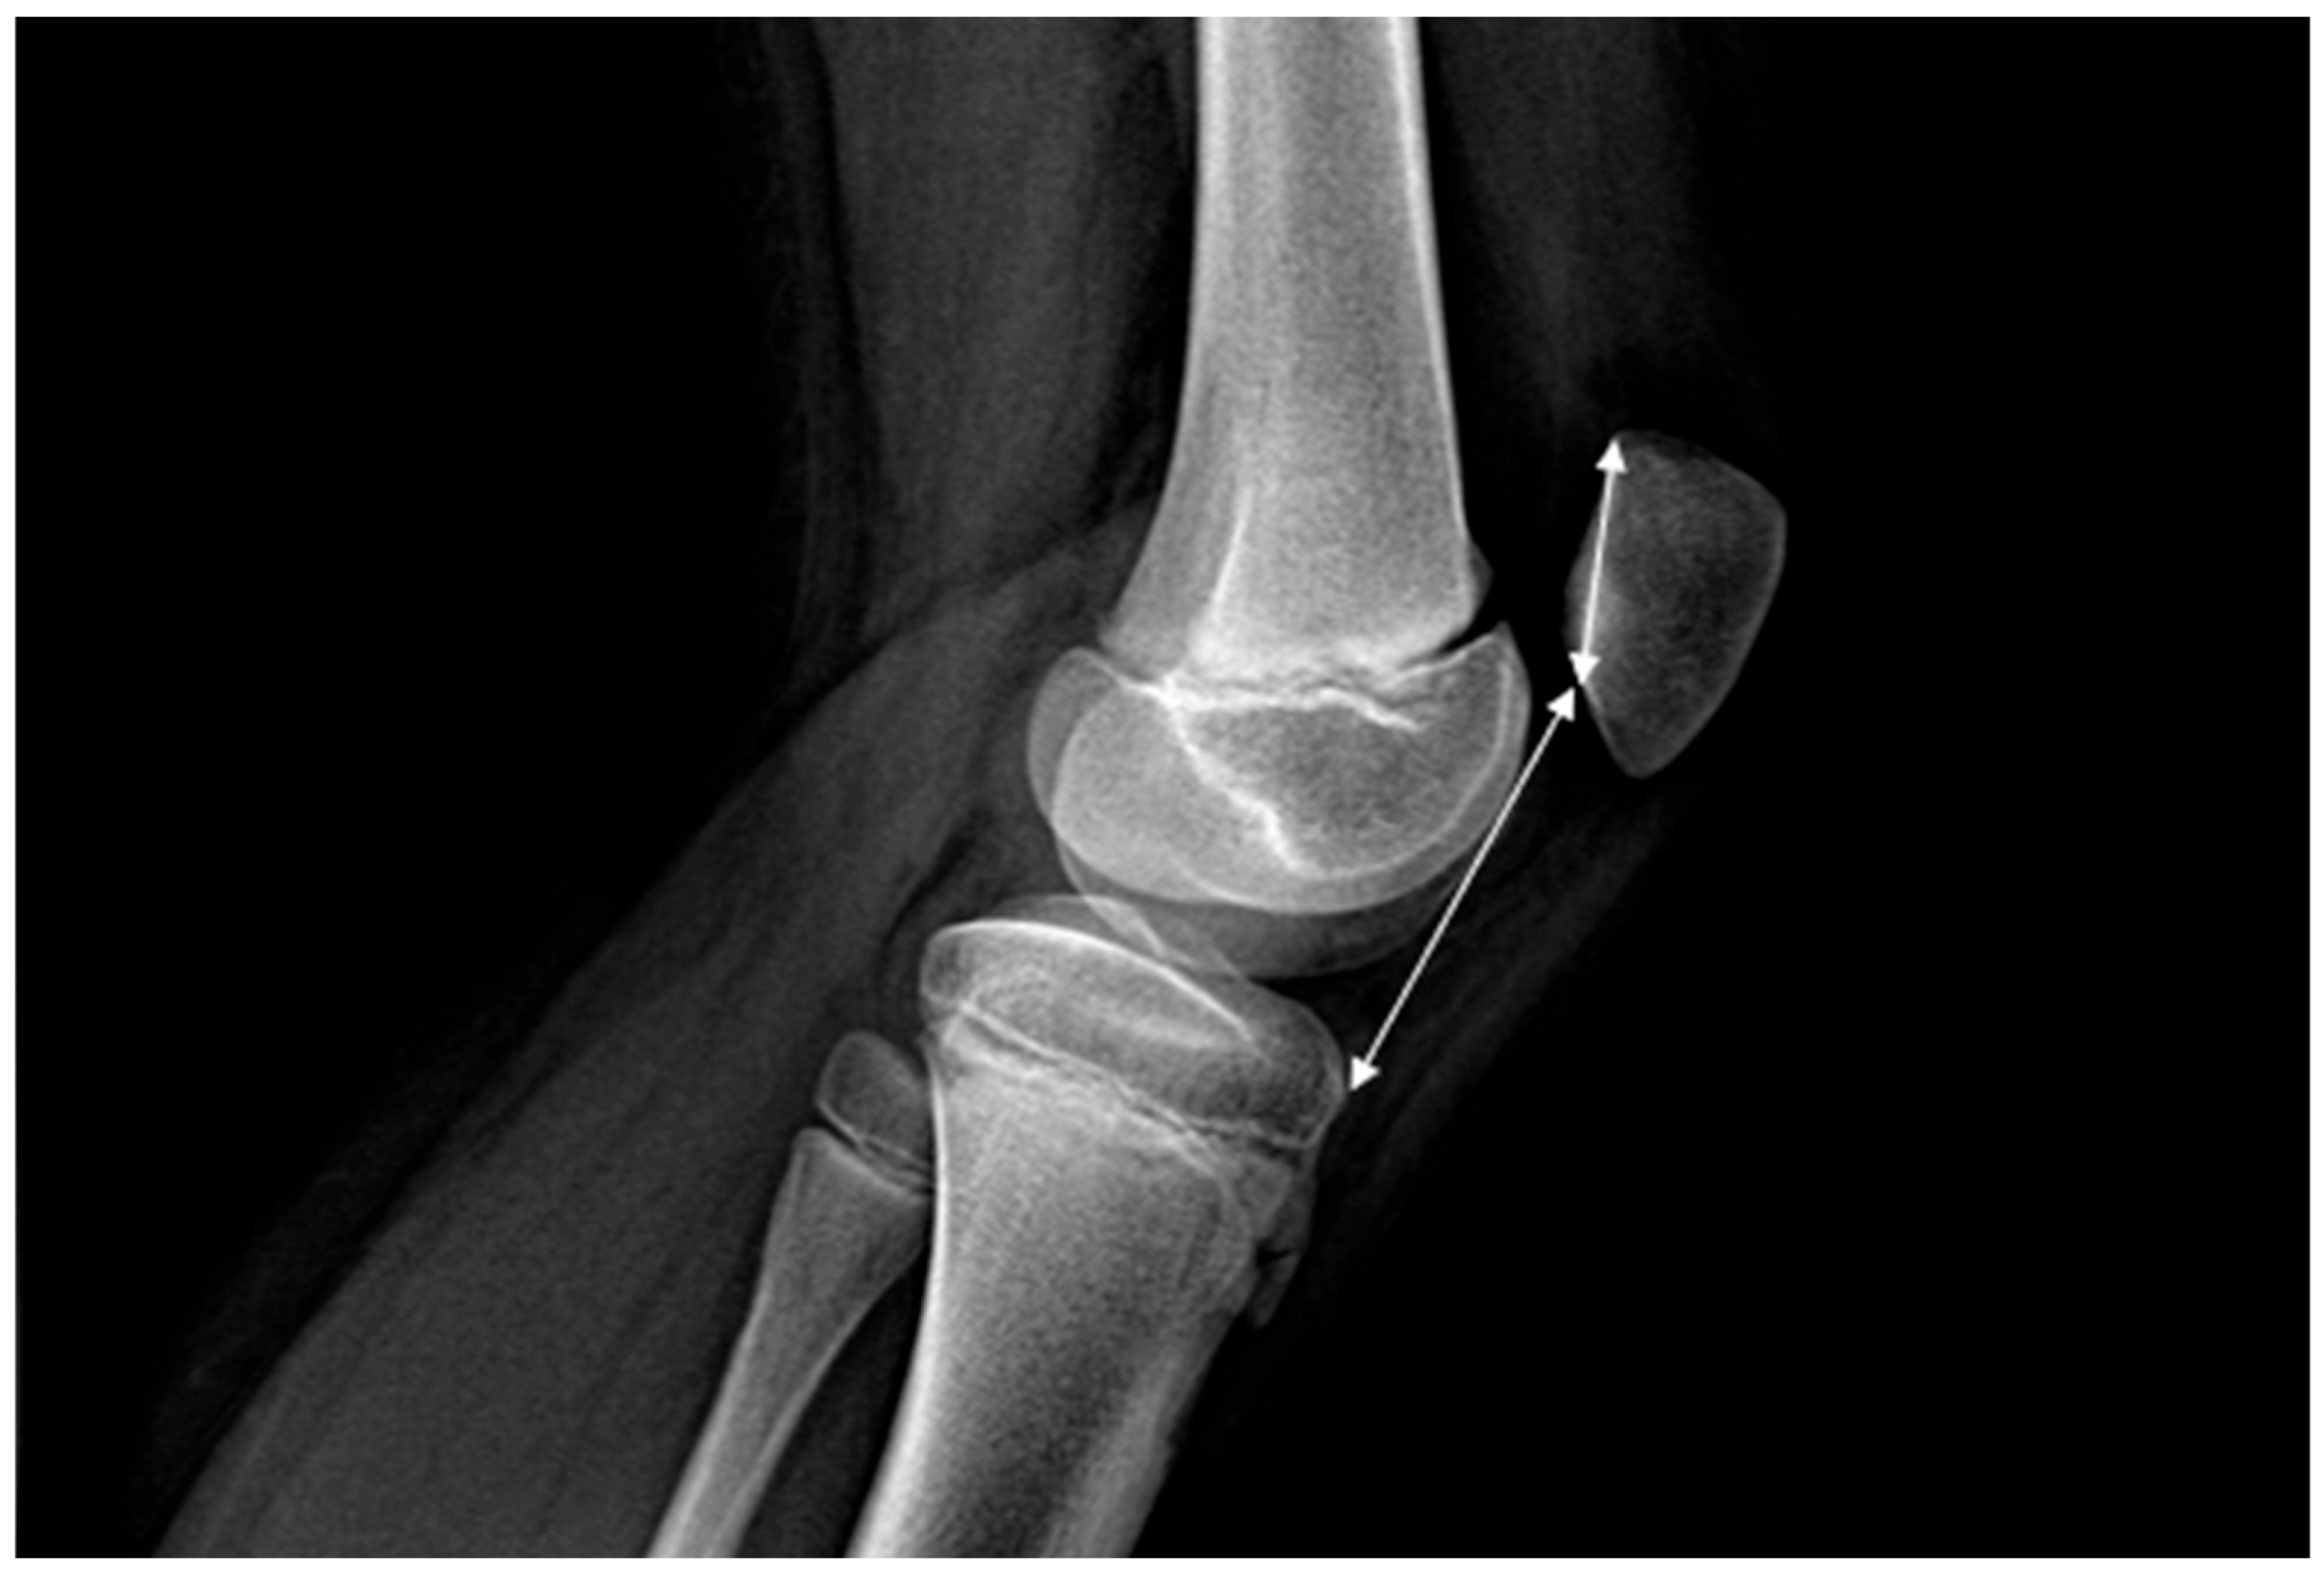

The following imaging variables were measured: patellar height, assessed using the Caton–Deschamps Index (CDI) with normal values between 0.6 and 1.2, trochlear dysplasia, classified according to Dejour types A–D, patellar dysplasia, according to Wiberg types I–IV, lateral condyle hypoplasia, TT–TG distance which is normal under 15 mm, measured on MRI or CT, sulcus angle normally ranging between 135° and 140°, and lateral patellofemoral angle (Laurin) which normally opens laterally, patellar tilt, knee valgus angle measured on AP ortoleg using hip–knee–ankle angle (HKA), femoral anteversion and tibial torsion, when available [3,10,11,12]. Figure 3 shows the necessary parameters to calculate CDI.

Figure 3. CDI represents the ratio between the length of the patellar articular surface and the distance from the anterior angle of the tibial plateau to the most inferior point of the patellar articular surface, measured on a lateral radiograph with the knee in 30 degrees of flexion.